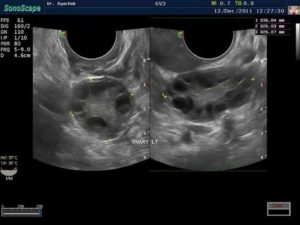

Эхопризнаки мультифолликулярных яичников

Врач ультразвуковой диагностики при проведении ультразвукового обследования без труда определяет МФЯ. Их основные эхографические признаки мультифолликулярных яичников:

- Размер яичников незначительно превышает норму;

- Эхогенность (способность ткани по-своему отражать ультразвуки) у яичников меньше, чем у матки;

- Множественные (более 20) антральные фолликулы (структуры с высокой вероятностью дозревания), их размер не превышает 9 мм;

- Доминантный фолликул не имеет утолщенной капсулы;

- Расположение антральных фолликулов диффузное (разбросанное).

Мультифолликулярность и поликистозность на узи